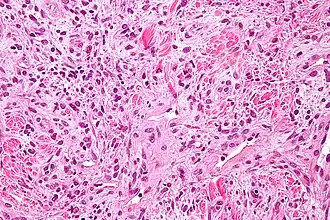

Hemangiopericytoom

Hemangiopericytoom is een zeldzame vasculaire neoplasie, of abnormale groei, die goedaardig of kwaadaardig kan zijn. In zijn kwaadaardige vorm kan er uitzaaiing optreden naar de longen, lever, hersenen en armen en benen. Het manifesteert zich meestal in het dijbeen en proximale scheenbeen als een osteosarcoom, en wordt meestal aangetroffen bij oudere personen, hoewel er gevallen zijn gevonden bij kinderen. Hemangiopericytoom wordt veroorzaakt door de overmatige lagen pericyten rond onjuist gevormde bloedvaten. De diagnose van deze tumor is moeilijk vanwege het onvermogen om pericyten te onderscheiden van andere soorten cellen met behulp van lichtmicroscopie. De behandeling kan chirurgische verwijdering en radiotherapie omvatten, afhankelijk van de mate van botpenetratie en het stadium in de ontwikkeling van de tumor.[40]